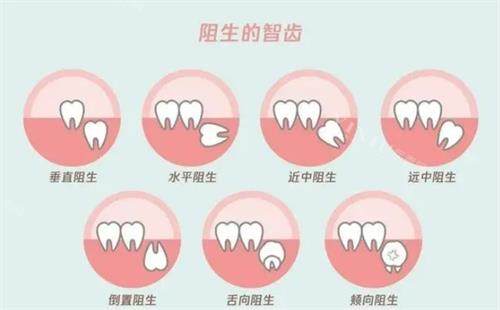

很快就轮到我就诊,接诊的是一位经验充足的医生。他先拿着口镜仔细检查了智齿的情况,又安排我拍了口腔 CT。看着电脑屏幕上歪着长的智齿,医生指着片子耐心解释:“你这颗智齿是水平阻生,顶着前面的牙齿,不仅容易发炎,时间久了还会把邻牙顶坏,确实得拔掉。” 听到 “阻生” 两个字,我心里 “咯噔” 一下,紧张地问:“会不会很疼啊?” 医生笑着安慰:“放心,咱们打了麻药就跟睡一觉似的,过程不会难受,我手法快,尽量减少你的不适感。” 听他这么一说,我稍微安心了些。